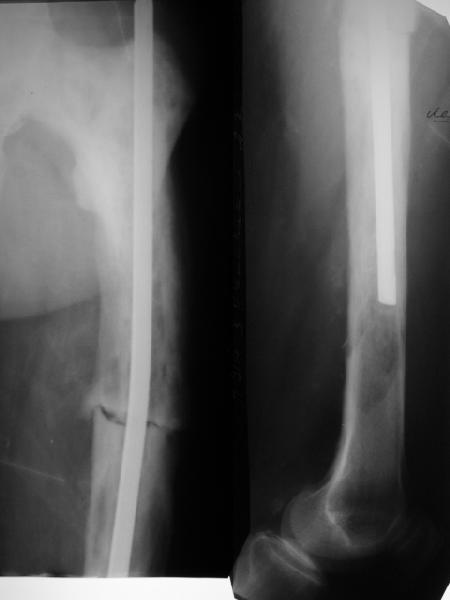

Мужчина 76 лет в феврале оперирован в одной из горбольниц - открытый интрамедуллярный остеосинтез бедра, травму получил при падении. К нам поступил с болью и ощущением подвижности в месте перелома, особенно при ротационных движениях. На снимках, кроме несращения, еще и изменение костной структуры. Чем оно обусловлено? Это не болезнь Педжета?Планируем бедро закрыто перештифтовать. Должно ли это состяние кости как-то повлиять на план? Рассверливать ли канал? Насколько? Гвозди есть от 9 до 12 мм.

I believe its Pagets. The bone looks larger than normal, along with coxa vara, which is characteristic. Check his alkaline phophatase. In rare instances, you can see aggressive lytic disease (unlikely here), which requires medical Rx to quiet down. Get out your reamers, and put

a big nail in him- the biggest his canal will take. Make it longer, and lock if you don't believe the fixation is snug.

>From the appearance of the x-rays and the description of a fracture after minimal trauma, I would be very concerned about a neoplastic

process. Odds would favor something metastatic and appearance might suggest a combined blastic-lytic lesion. I am particularly concerned about the lytic appearance distal to the end of the rod. I would work up the patient for both neoplastic and metabolic process before proceeding.

The femur is Pagetic.

Aim to use a strong reamed locked nail, as the femur is bowed and union may be slow.

Be prepared for greater than usual blood loss.

I think it could be a neoplasy (i.e. a giant cells sarcoma, infact the cortex seems to be thinner or destroyed.). Then the fracture you've seen synthesized with a nail could be a pathologic one. I see on x-rays a destruction of the medullary cavity too.

Agree, it is likely Paget's. The larger nail, reaming and locking, both distally and poximally, will do the job. Make sure pre op there is no infection. Good luck.